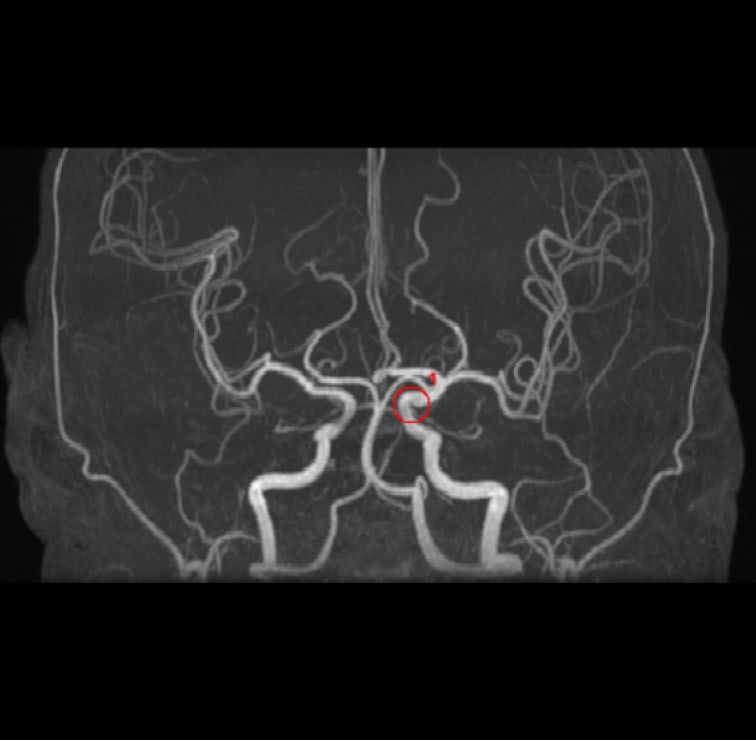

解析事例

内頚動脈-後交通動脈